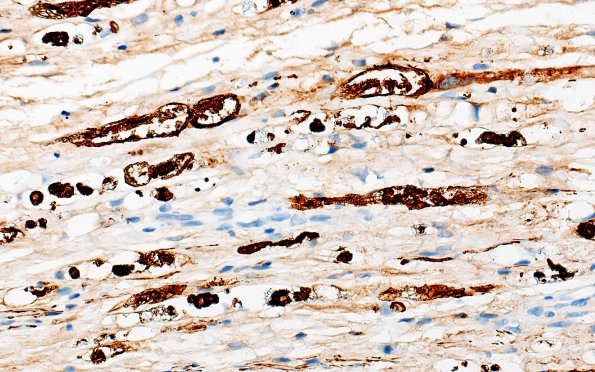

7C3 Ovoids (Case 7) NF 40X 2

Sections show progressively increased magnification of ovoids stained for neurofilaments. (NF IHC)